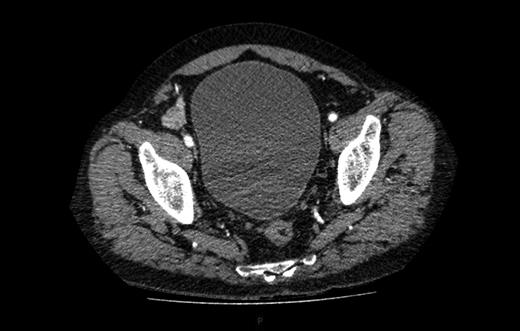

A computed tomography (CT) of the abdomen and pelvis was performed. This showed a grossly distended urinary bladder and compression of the sigmoid colon against the sacral promontory causing bowel obstruction (Figs 1 and 2, respectively) as well as a 4.9 cm abdominal aortic aneurysm without any signs of a rupture (Fig. 3). The plan was to consult our vascular colleagues regarding management of the AAA once the obstruction had settled.

The initial CT scan of the abdomen showing a large distended bladder.